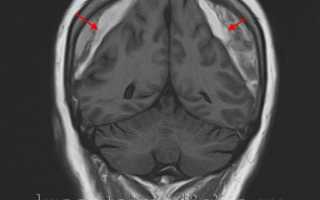

image

МРТ головного мозга. Массивная двухсторонняя хроническая субдуральная гематома.